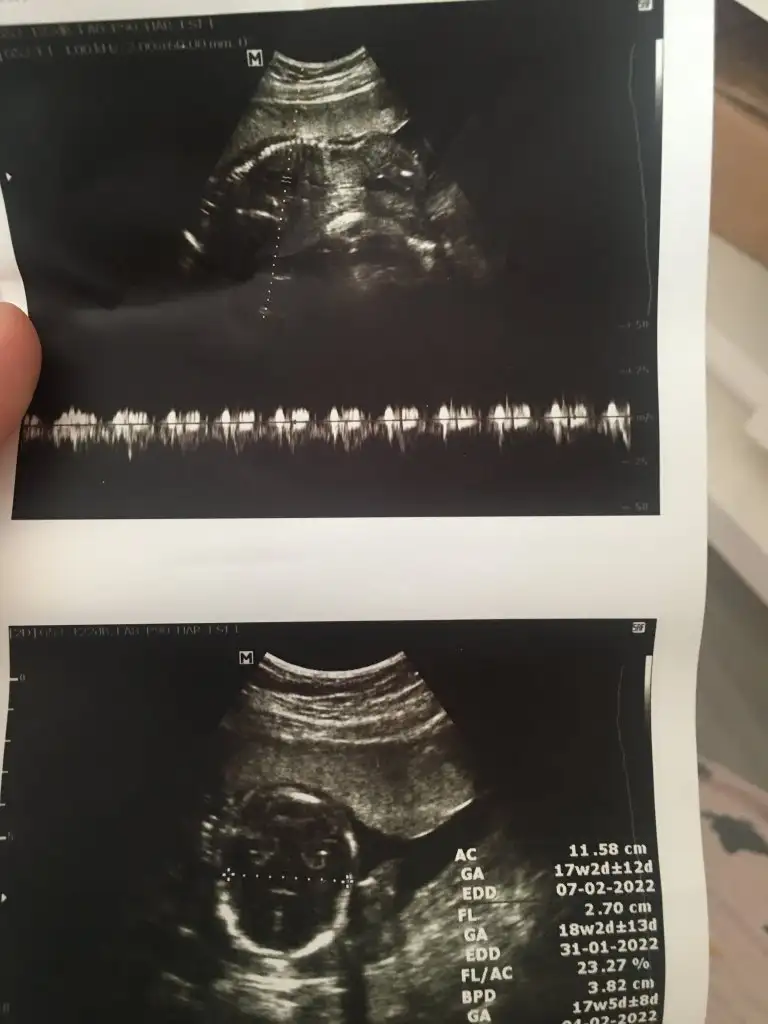

Canım bi bakar mısın yandan net görüntü yok maalesef 18 haftalık doktor erkek dedi ikinci resimde işaretlediği kısma pipi dedi sence de erkek mi bundan önce ki doktor kıza benzetmiştiKız gibi

Canım bakar mısın benim attığımı daCanım bi bakar mısın yandan net görüntü yok maalesef 18 haftalık doktor erkek dedi ikinci resimde işaretlediği kısma pipi dedi sence de erkek mi bundan önce ki doktor kıza benzetmişti

Ben 11 12 13 haftalar bakiyorum varsa paylaşınCanım bi bakar mısın yandan net görüntü yok maalesef 18 haftalık doktor erkek dedi ikinci resimde işaretlediği kısma pipi dedi sence de erkek mi bundan önce ki doktor kıza benzetmişti

Emin olamadım sanki erkek gibi

Doktor da emin değil ama erkek gibi sanki dediEmin olamadım sanki erkek gibi